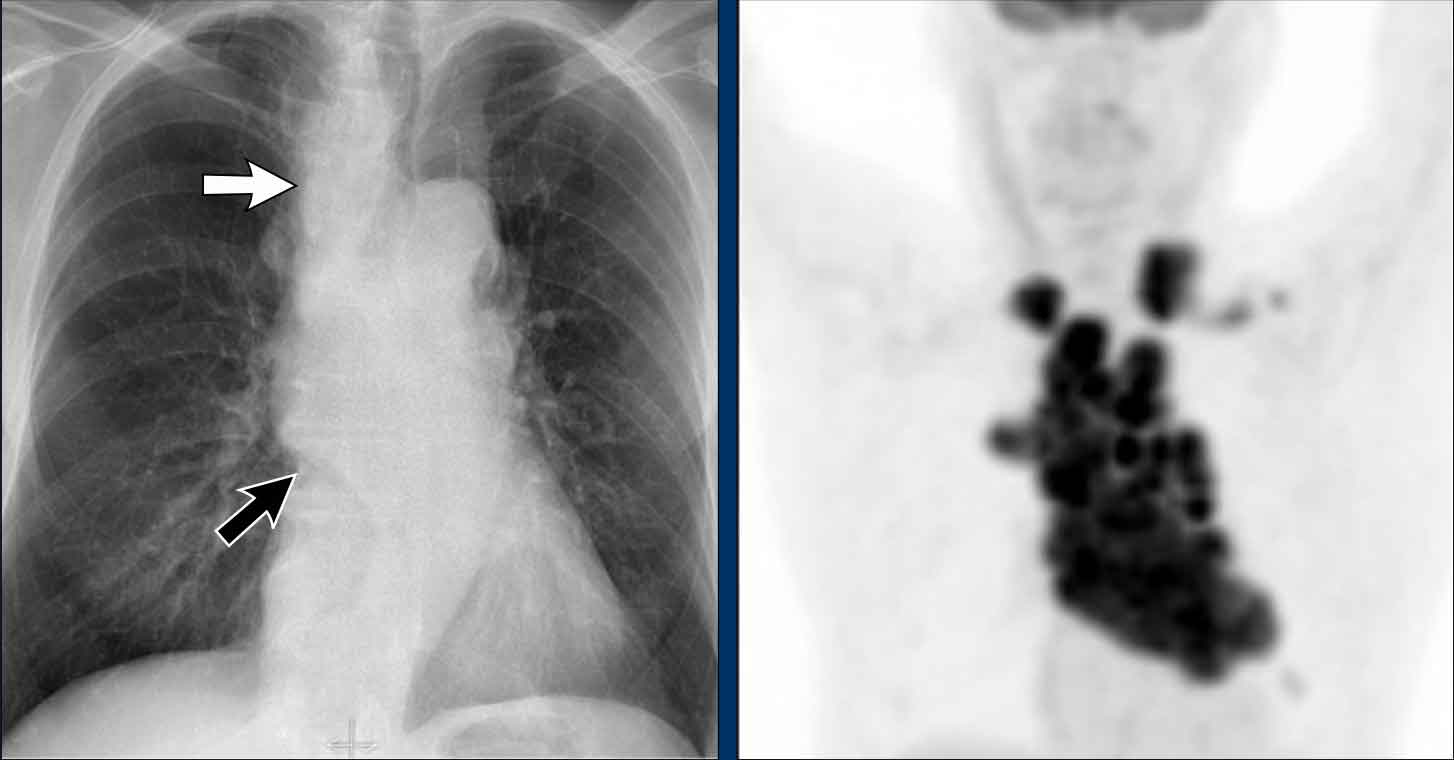

Hidden area (5): Mass Behind the First Rib

In some patients, an accessory joint at the anterior aspect of the first rib may simulate a mass, as we learned earlier.

However this area is also a "hidden zone", where true lesions can be masked.

- In this case, a small lung carcinoma was obscured by the left first rib on the PA view.

- On the lateral film, the lesion is visible in the retrosternal space.

Continue with the PET-CT...

Subsequent PET-CT imaging confirmed a hypermetabolic tumor (arrow), with metastases to the bone and liver.

- Diagnosis was confirmed via biopsy of an osteolytic metastasis in the iliac bone.